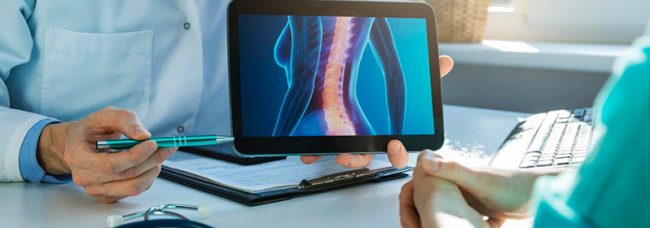

Conheça os possíveis tratamentos para os principais problemas na coluna: 1º Tratamento Conservador (medicamentos, fisioterapia, RPG, acupuntura, pilates, hidroginástica) 2º Infiltração na Coluna ou Bloqueios 3º Endoscopia de Coluna ou Cirurgia Endoscópica da Coluna 4º Cirurgia Minimamente Invasiva da Coluna 5º Cirurgia Aberta com Artrodese e Fusão das Vértebras

Para uma decisão em relação ao tratamento da Hérnia de Disco, devem ser levadas em conta as características de cada paciente, que por sua vez deve ter uma compreensão plena da sua doença e das alternativas de tratamento indicadas pelo médico (da mais conservadora até a cirurgia).